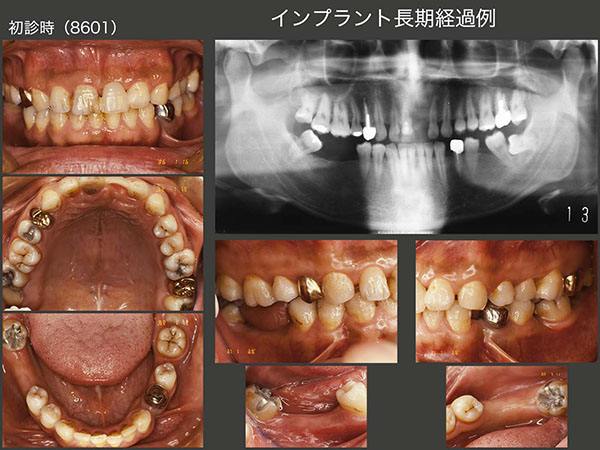

1.インプラント長期経過例

1986年1月初診,31歳男性.当時私は,東京歯科大学病院に勤務しており,その時に担当した患者さん.主訴は右下67の欠損補綴を希望.大学には83年,日本で初めてブローネマルク・インプラントが導入された.歯科医師になって6年目の駆け出しの私としては,ぜひインプラントを用いた治療を行ってみたく,うずうずしていた.丁度同級生にインプラントに詳しい先生がいたので,助手についてもらい,ITIインプラントを植立した.

当時のインプラントはネック部が細く,大きな咬合力には耐えられないと判断し,咬合面をできるだけ小さく製作した.今のインプラントの太さならばもう少し大きく製作できる.しかし小さく製作したことがインプラントに加わる力の軽減に繋がり,インプラントの長期保存に貢献した一つの理由なのかもしれない.

1997年まで,大学病院で定期健診を行っていた.その後暫く拝見することができなかったが,2008年以降,私の診療室まで何時間もかけて通院してくださるようになった.右下のインプラントは30年経過しても順調だが,この理由は2つあると考えている.まず,先にも述べたが咬合面の面積を小さく製作したことが挙げられる.つぎに,インプラントでは嚙んだ時の食感が少ないことから,上下顎に歯のある左側で主に咀嚼していたからと考えている.しかし患者さんは,右側でも咬んでいるとおっしゃっているし,左側の歯に特に問題が生じていないことから,確かに両側で咬んでいるのかもしれない.